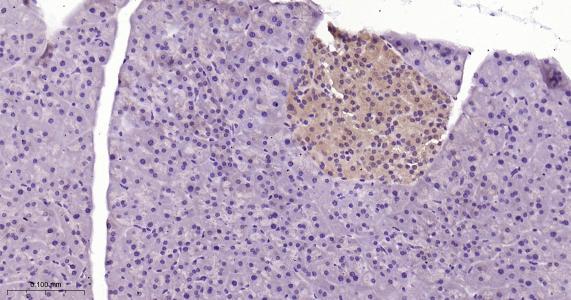

Paraformaldehyde-fixed, paraffin embedded Rat Pancreas; Antigen retrieval by boiling in sodium citrate buffer (pH6.0) for 15 min; Antibody incubation with TXNRD1 Monoclonal Antibody, Unconjugated(bsm-61558R) at 1:200 overnight at 4°C, followed by conjugation to the bs-0295G-HRP and DAB (C-0010) staining.